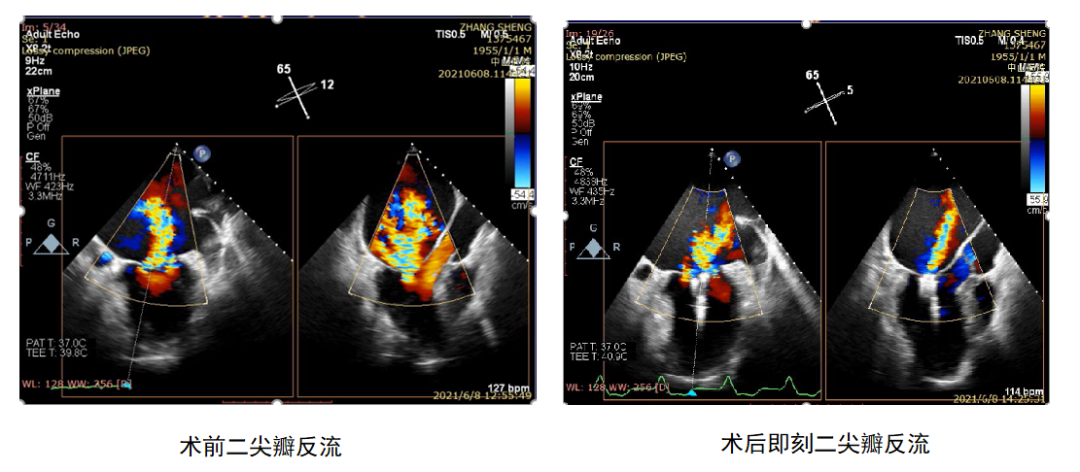

接受手术的是一位66岁男性患者,来院就诊时病情已十分严重。生命体征处于不平稳状态,心率140-150bpm,血压85/50mmHg,端坐呼吸,半月前在外院治疗使用大量利尿剂小便仍只有数百毫升。术前超声显示:左心房巨大(12cm),左心室扩大(70mm),LVEF 35%,前后瓣拴系导致A2P2的两侧极重度二尖瓣反流(VC 12*18mm)。由于患者无法耐受术前食道超声检查,故未行详细术前食道评估,紧急行ValveClamp术。

术后患者反流量即刻减少70%,血压提升至105/65mmHg,心率降低至105bpm。经过后期数天药物调整,患者病情进一步好转,左心房、左心室明显减小,LVEF提高至 48%,小剂量利尿剂尿量即可达到2000ml,拟于近日出院。